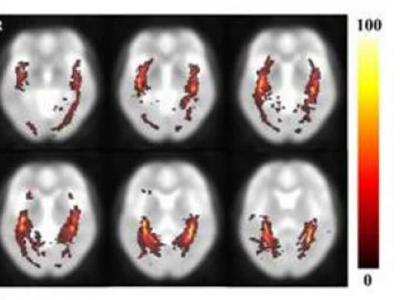

首次验证健康人大脑视放射的定量容积数据

健康人OR概率通路图(图中颜色代表OR通路概率) (神秘的地球)据EurekAlert!:...